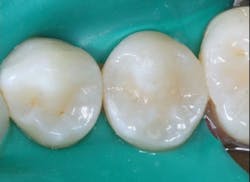

Figure 6: Finished restoration. Restorations accomplished in this manner will not have postoperative tooth sensitivity.